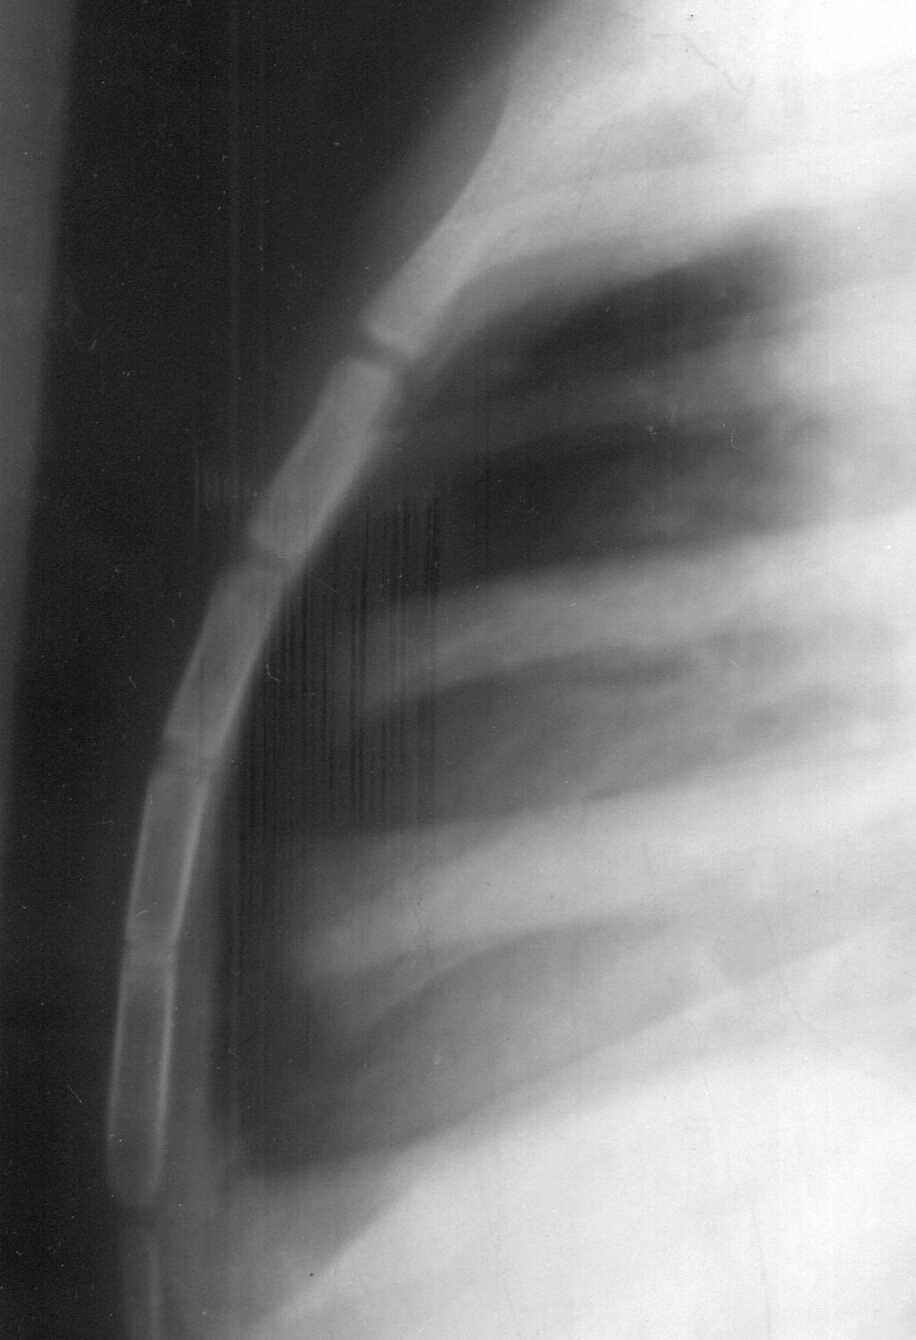

![Fig 1. Lateral view of the chest showing sternum and its pieces in a 16 year old male [35 kb]](others/ug_pics/1lr.jpg) |

Fig 1. Lateral view of the chest showing sternum and its pieces in a 16 year old male

This is usually a neglected bone even by forensic practitioners engaged in the determination of age. But it can give strikingly accurate ages. Figure 1 is an example. This case was brought to the author for age estimation. A lateral X-ray of chest was advised. All the four pieces of sternum can be seen clearly.

The third and fourth piece have almost united, which allowed the author to opine on the age as around 15 years. This was later found to be true from other evidences. Figure 2 shows the usual ages of fusion of other parts of this bone.